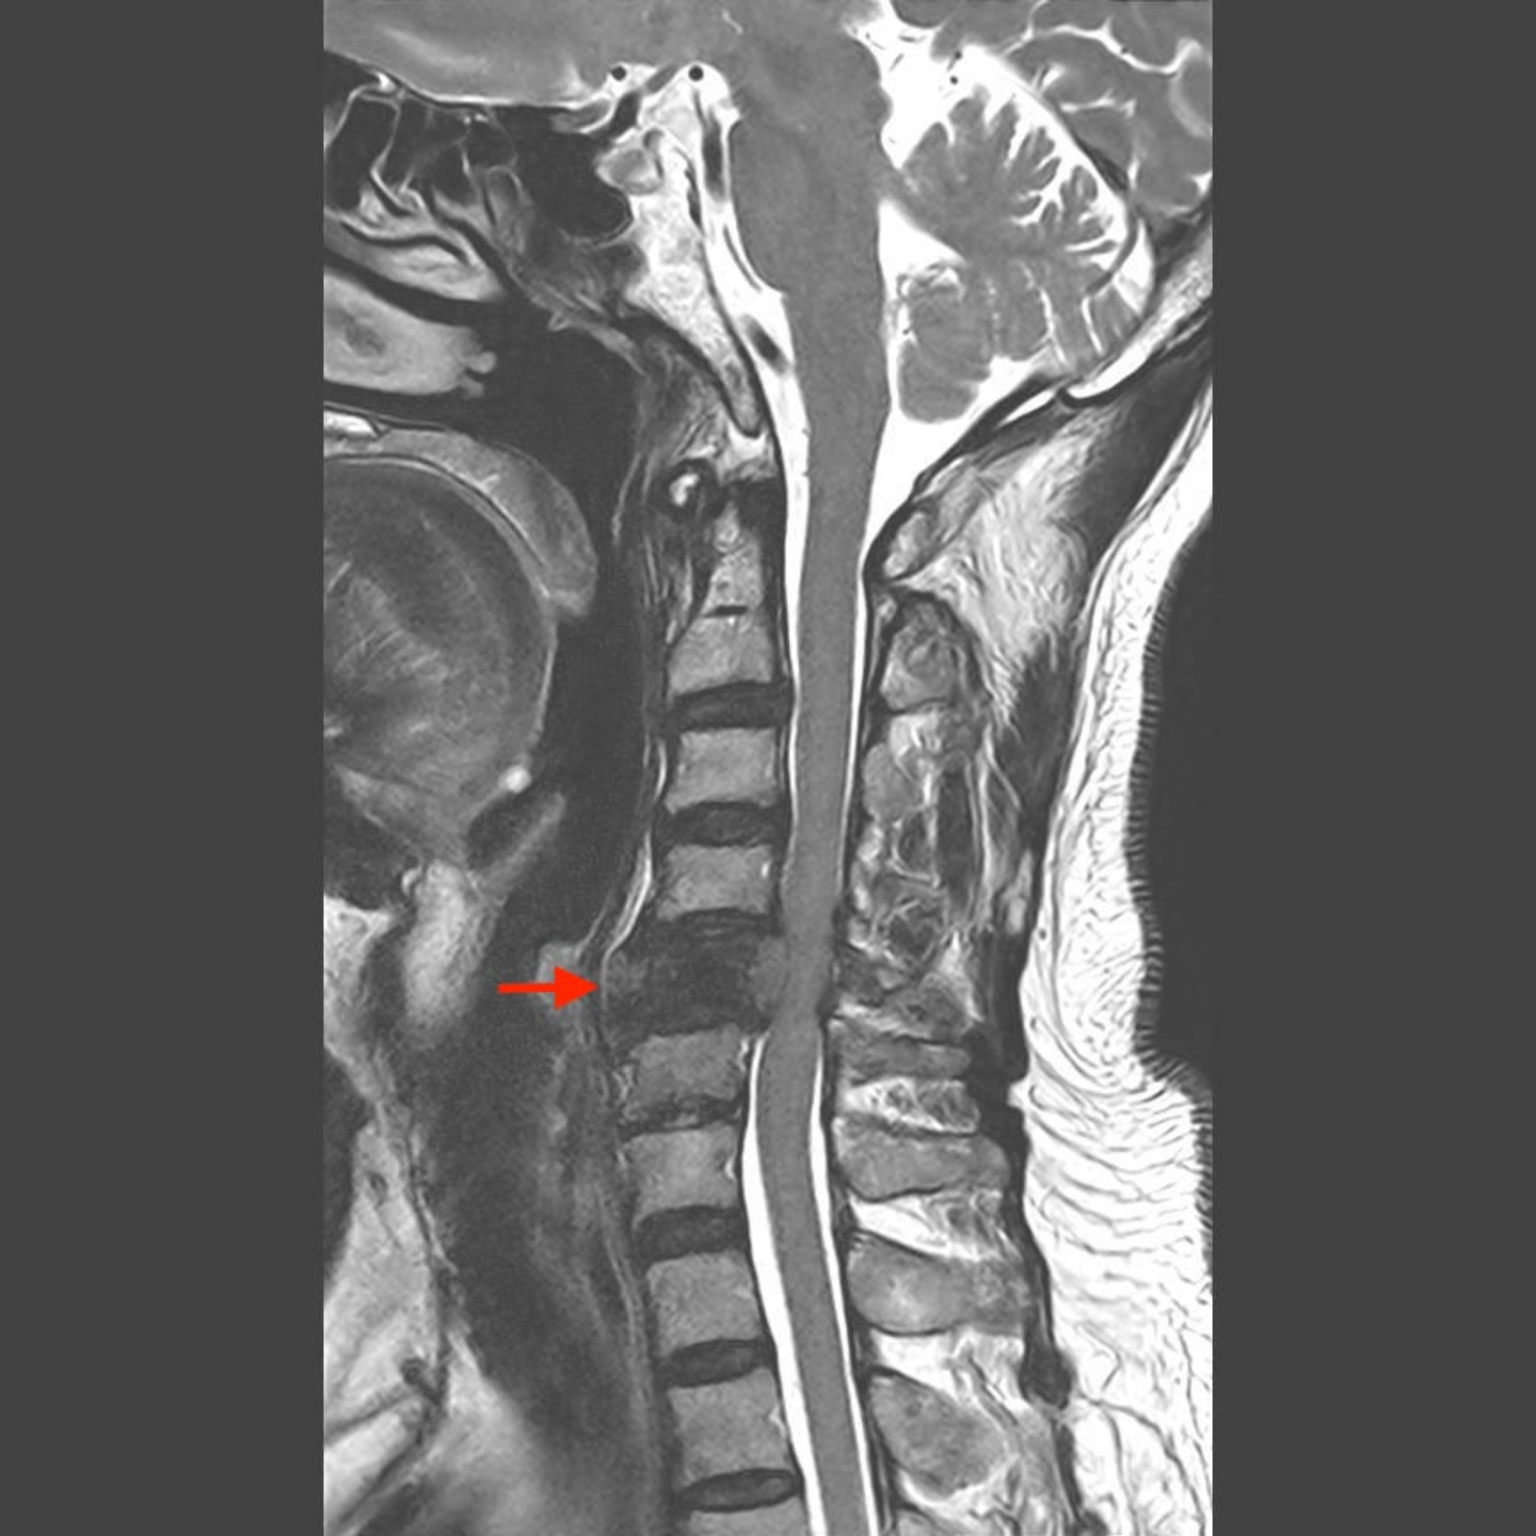

醫師能夠提供的服務,最重要的是診斷 : 頸椎狹窄的病因有許多,從發生率最高的椎間盤突出(俗稱骨刺)(圖2)、亞洲人(日本、韓國、台灣) 較常發生的後縱韌帶鈣化、到惡性腫瘤骨轉移(常見的攝護腺癌、肺癌、乳癌)(圖3)都有可能。從最基本的頸部X光到精密的核磁共振,醫師會依照症狀選擇合適的診斷工具。